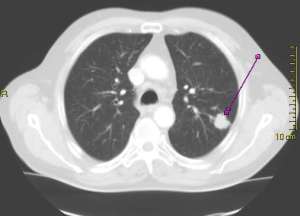

Food for thought: What is the rate of false positive rate of CT scan for lung cancer screening?

Click here and read the results section of this abstract for the answer. Shocking isn’t it.